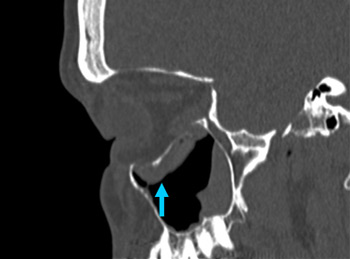

Right orbital blow-out fracture on CT-scan; sagittal reformat

From the personal collection of Dr Alistair Cobb